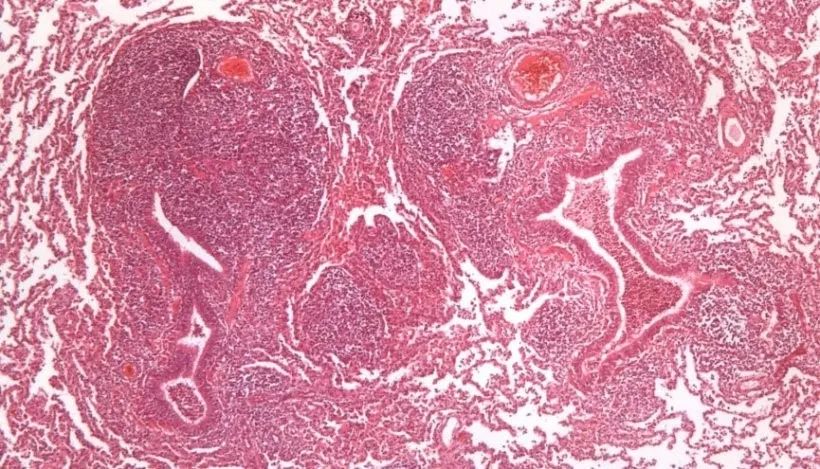

肺炎支原体黏附到呼吸道上皮细胞纤毛,导致纤毛损失,改变黏膜纤毛功能,导致肺脏的分泌物、吸入的灰尘颗粒和病原不能被清理出呼吸道,而进入下呼吸道,影响猪的呼吸过程。肺炎支原体导致支气管性间质肺炎,肉眼可见肺脏间叶和心叶组织红色实变,与其它正常区域区分明显(图1)。在显微镜检下,肺炎支原体导致支气管、细支气管和血管周围淋巴组织增生(图2)。

图2. 肺炎支原体引起的支气管周围淋巴组织增生